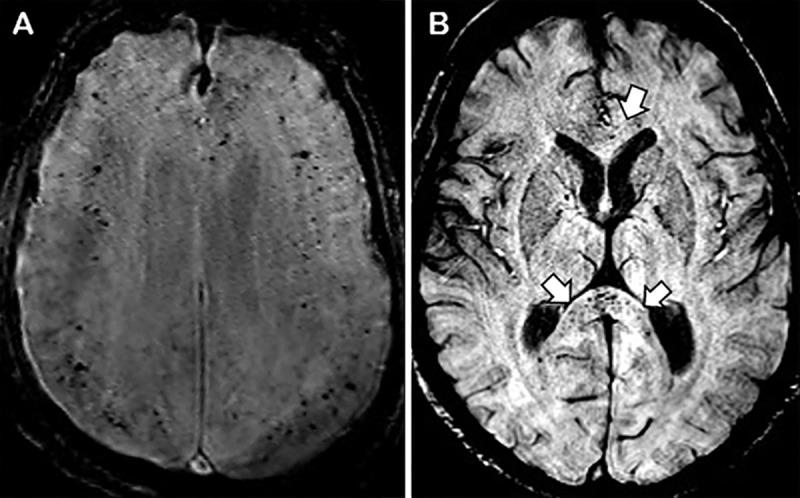

Diffuse leukoencephalopathy and juxtacortical and/or callosal microhemorrhages were brain imaging features in critically ill patients with coronavirus disease 2019. Coronavirus disease 2019 (COVID-19) has been reported in association with a variety of brain imaging findings such as ischemic infarct, hemorrhage, and acute hemorrhagic necrotizing encephalopathy. Herein, the authors report brain imaging features in 11 critically ill patients with COVID-19 with persistently diminished mental status who underwent MRI between April 5 and April 25, 2020. These imaging features include confluent T2 hyperintensity and mild restricted diffusion in bilateral supratentorial deep and subcortical white matter (in 10 of 11 patients) and multiple punctate microhemorrhages in juxtacortical and callosal white matter (in seven of 11 patients). The authors also discuss potential pathogeneses.

弥漫性脑白质病和皮质下及/或胼胝体微出血是 COVID-19 危重症患者的脑部影像学特征。有报道称,COVID-19(新冠肺炎)与多种脑部影像学表现相关,如缺血性梗死、出血和急性出血性坏死性脑病。在此,作者报告了 11 例 COVID-19 危重症患者的脑部影像学特征,这些患者的精神状态持续减退,于 2020 年 4 月 5 日至 4 月 25 日期间接受 MRI 检查。这些影像学特征包括 11 例患者中有 10 例双侧大脑半球深部和皮质下白质存在融合性 T2 高信号和轻度弥散受限,以及 7 例患者存在皮质下和胼胝体白质内多发性点状微出血。作者还讨论了潜在的发病机制。